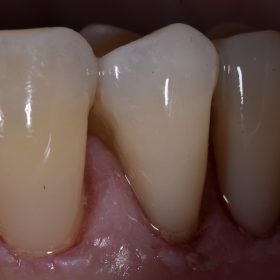

Cosmetic Dentist Auckland | Composite Artistry | Composite Bonding | Partial Veneer

#statusposttrauma #barfight Kerr Harmonize shades A1E, A1D, Trans SuperClear, XL1 Enamel and White Tint #SkulptingSkool102 #TamDentalGroup